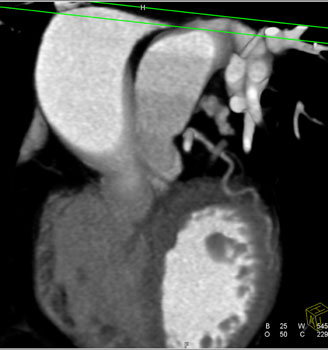

![]() | Question 20: The patient had atypical chest pain and the CTA was done to rule out a critical stenosis. What is the diagnosis? |